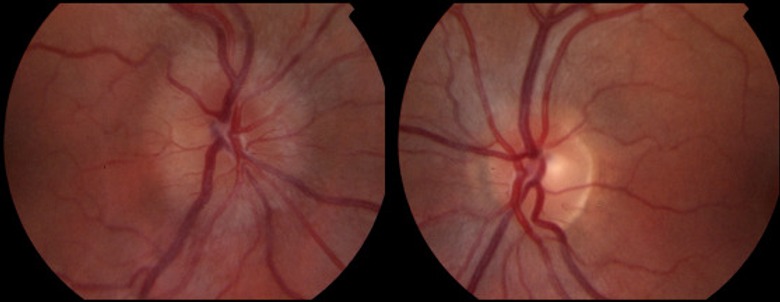

3.SEQUENTIAL Fundus Photography: This imaging technique captures detailed images of the back of the eye, including the optic nerve, retina, and blood vessels, helping to document and monitor changes associated with neuro-ophthalmic conditions like papilledema, optic nerve drusen, and diabetic retinopathy.

ISCHEMIC OPTIC NEUROPATHY

AION (Arteritic Anterior Ischemic Optic Neuropathy) and NAION (Non-Arteritic Anterior Ischemic Optic Neuropathy) are conditions that affect the optic nerve, leading to sudden vision loss. They differ mainly in their underlying causes and treatments.

Swollen Optic Disc: An eye examination may reveal swelling of the optic disc, where the optic nerve enters the eye.